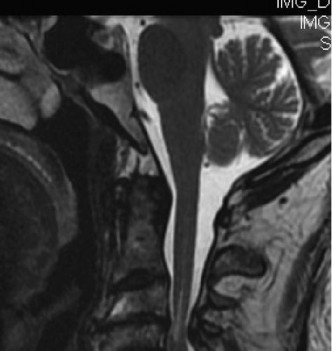

- MRI: The gold standard to assess spinal cord pathology (edema, hemorrhage, compression, contusion) and evaluate soft tissue compressive lesions (disc herniation, ligamentum flavum hypertrophy). Crucially, it delineates the extent and location of cord compression.

- CT Scan: Provides detailed bony anatomy, identifies fractures, osteophytes, and can assess spinal canal dimensions. CT angiogram may be considered if vertebral artery injury is suspected, particularly in fracture-dislocations.